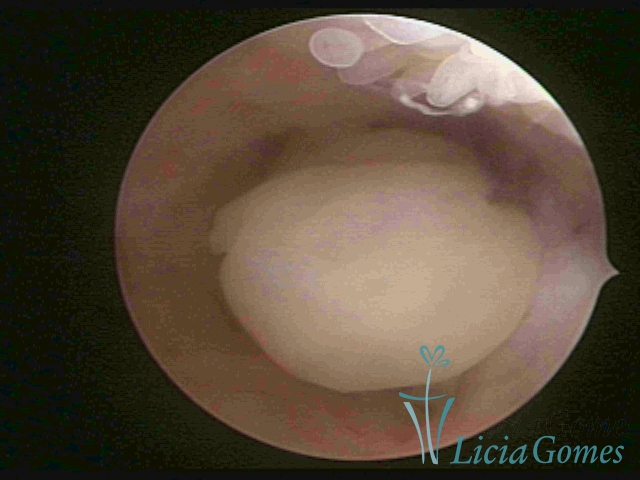

PÓLIPOS ENDOCERVICAIS

São tumores benignos, resultantes da proliferação focal reativa aos processos inflamatórios ou à situações de hiperestrogenismo, e podem ter sésseis (com a base de implantação larga) ou pediculados do epitélio.